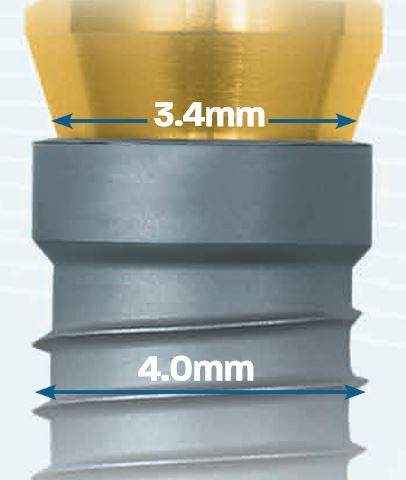

El implante T3® PRO de ZimVie® es la versión de nueva generación del implante cónico, diseñado para ofrecer una alta estabilidad primaria y posibilidad de función inmediata, reduciendo los tiempos de tratamiento sin sacrificar los resultados estéticos ni la salud ósea a largo plazo.

Su ingeniería incluye un núcleo totalmente cónico con roscado progresivamente más profundo hacia el ápice, lo que permite un contacto inicial hueso-implante alto y una inserción controlada. Además, cuenta con una superficie híbrida contemporánea, destinada a favorecer la osteointegración y mantener el nivel óseo periimplantario.

El sistema conserva la conexión interna Certain® compatible con la tecnología SureSeal™ y “Platform Switching”, lo que asegura un sello fuerte entre implante y pilar. Esto ayuda a minimizar micromovimientos o filtraciones, factores importantes para la durabilidad y salud del implante.

El contacto inicial entre el hueso y el implante es el principal responsable de la estabilidad del implante. Las especificaciones de los implantes T3® de ZimVie® están sujetos a rigurosas tolerancias para ofrecer un íntimo ajuste entre el implante y la osteotomia, creando un sistema de implantes dentales que ayuda a conseguir estabilidad primaria.